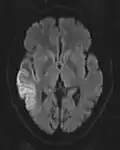

DWI showing cortical ribbon-like high signal consistent with diffusion restriction in a patient with known MELAS syndrome

DWI showing cortical ribbon-like high signal consistent with diffusion restriction in a patient with known MELAS syndrome